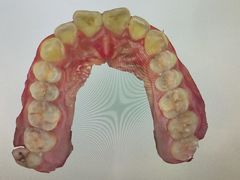

• 岳辰齿科(浦东长泰店)

• -岳辰齿科(浦东长泰店)

灼灼其桦_Lisa | 23-10-31